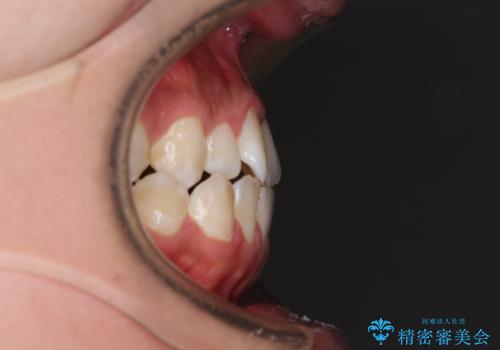

- 受け口傾向の咬み合わせと口元の突出感を気にして来院された患者様です。

受け口傾向特有の狭い上顎歯列であったため、歯列の拡大を補助装置で行い、下顎歯列全体を後方に移動させることとしました。

奥歯の咬み合わせを改善させた後、上下左右の小臼歯(下顎は残存乳歯)を計4本抜歯し、ワイヤー装置にて口元の突出感を改善しながら咬み合わせを整えることとしました。